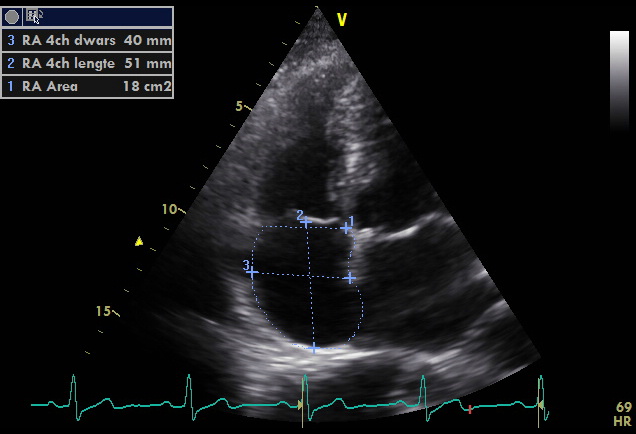

Right Atrium Echopedia

https://www.echopedia.org/images/e/ec/RAarea.jpg

Right Atrial Enlargement ECG Stampede

Adult Echocardiography Review Part 2 Ppt Download